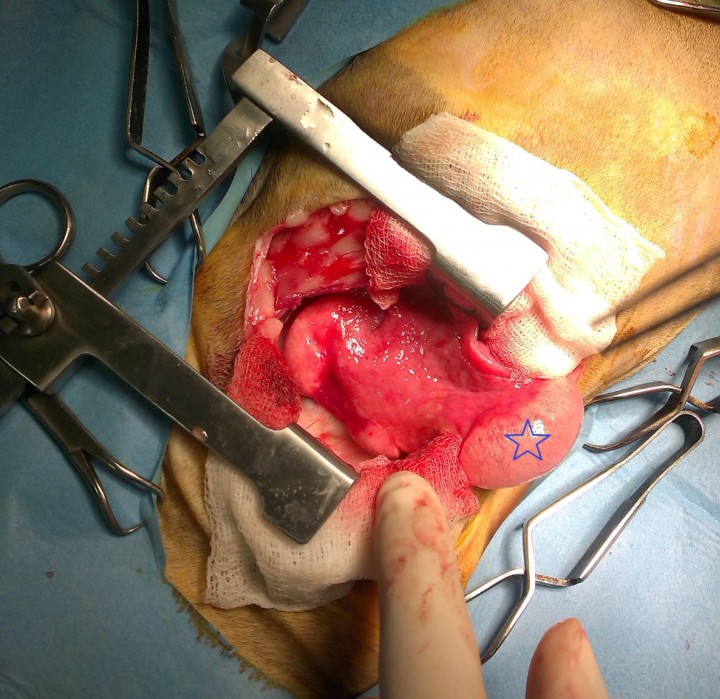

El estudio histopatológico revela un diagnóstico de severa neumonía lipídica endógena. Se observa la presencia de un elevado número de macrófagos de citoplasma de gran tamaño y aspecto espumoso por el acúmulo de vacuolas de lípidos en su interior (Fig. 7A). Estos macrófagos se localizan en el espacio alveolar ocupando por completo su luz (Fig. 7B), y también en el espesor en las paredes interalveolares produciendo un severo engrosamiento de las mismas.

<p>Imágenes microscópicas del pulmón. (<strong>A</strong>) Se observa población macrofágica con amplio citoplasma de aspecto espumoso por la presencia de vacuolas lipídicas (flecha) (Hematoxilina-eosina; 100x). (<strong>B</strong>) Se aprecia la ocupación del espacio alveolar por macrófagos cargados de lípidos (hexágonos). Escasas regiones muestran aire en su interior (estrellas). La misma población macrofágica invade los septos interalveolares (flechas). (Hematoxilina-eosina; 40x). Imágenes cedidas por Histolab.</p>

Imágenes microscópicas del pulmón. (A) Se observa población macrofágica con amplio citoplasma de aspecto espumoso por la presencia de vacuolas lipídicas (flecha) (Hematoxilina-eosina; 100x). (B) Se aprecia la ocupación del espacio alveolar por macrófagos cargados de lípidos (hexágonos). Escasas regiones muestran aire en su interior (estrellas). La misma población macrofágica invade los septos interalveolares (flechas). (Hematoxilina-eosina; 40x). Imágenes cedidas por Histolab.